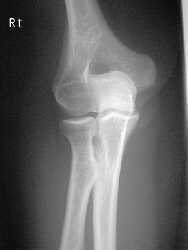

| AP Elbow | humerus is externally rotated because the epicondyles are not in profile |

| AP Oblique Elbow Internal Rotation | Insufficient obliquity |

| AP Oblique Elbow Internal Rotation | Excessive obliquity |

| AP Oblique Elbow External Rotation | forearm is not parallel to IR capitulum-radial joint is closed olecranon is not in the fossa |

| AP Oblique Elbow External Rotation | Underrotation distal forearm slightly elevated |

| AP Oblique Elbow External Rotation | Overrotation |

| AP Elbow | ANATOMY: distal humerus - proximal forearm CRITERIA: slight superimposition of proximal radius/ulna humeral epicondyles in profile open joint space POSITIONING: CR perpendicular @ midelbow |

| Medial Oblique Elbow | ANATOMY: proximal radius/ulna, distal humerus, medial epicondyle and trochlea CRITERIA: coronoid process in profile radial head and neck should superimpose the ulna olecranon process seen within olecranon fossa POSITIONING: CR perpendicular @ midelbow |

| Lateral Oblique Elbow | ANATOMY: open joint space, radial head, neck, tuberosity, and capitulum CRITERIA: radial head, neck, and tuberosity are free of superimposition humeral epicondyles and capitulum in profile POSITIONING: CR perpendicular @ midelbow |